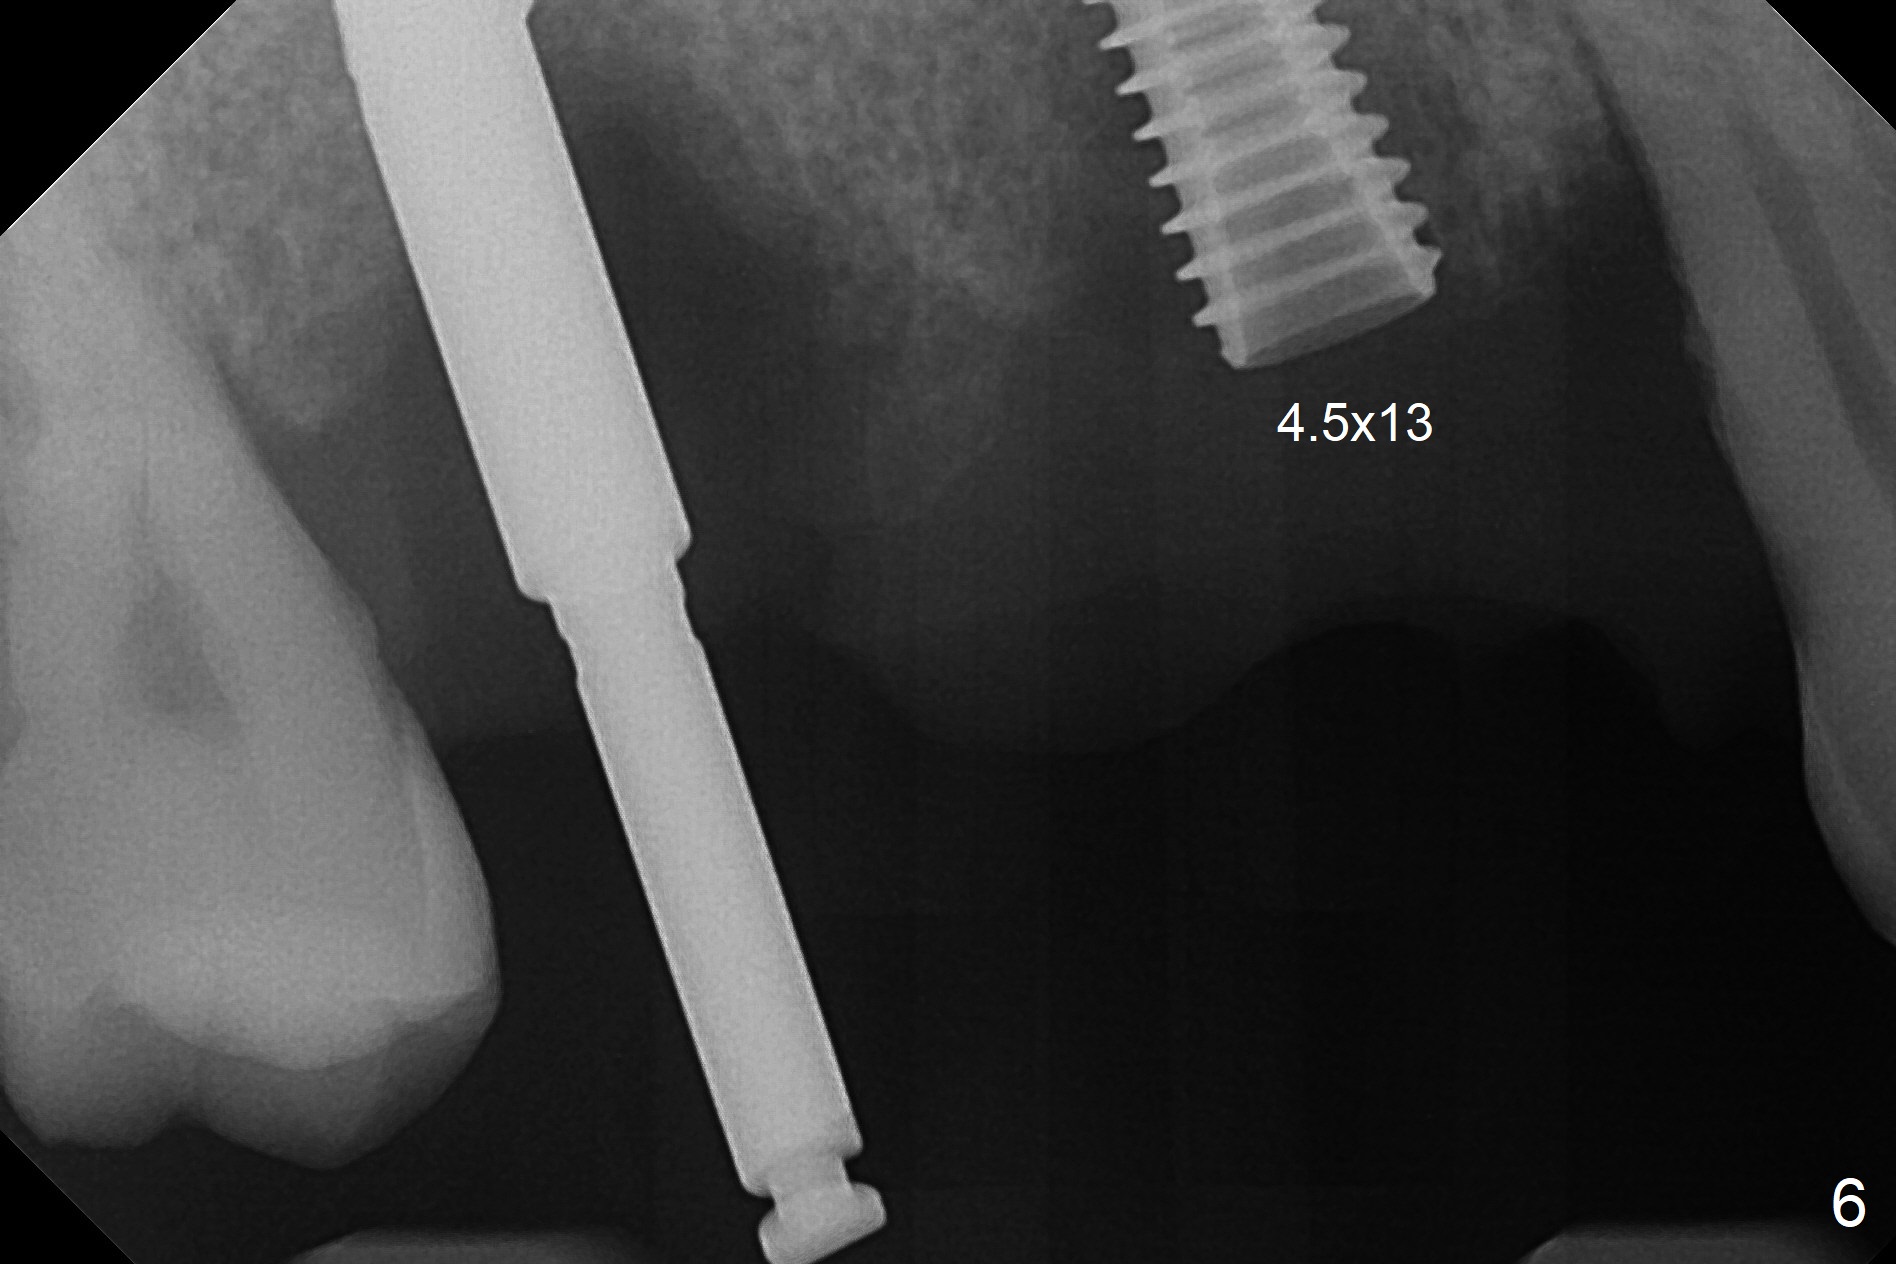

The 36-year-old man (ex-smoker, quit for 4-5 years) insists upon #3 and 5 extraction first for implants, in spite of more severe infection at #7, 14,19,30 (Fig.1-4). The gingiva around #23-26 implants is healthy 3 weeks postop (Fig.5). The initial depths at #3 and 5 are 8.5 mm (bone-level) and 18 mmm (gingiva-level (13 mm (implant length) + 5 mm cuff), respectively. When a drill penetrates the sinus floor, confirm the depth. After use of 3.8 mm drill, 4.5 mm tap drill is inserted at #3 without stability, while a 4.5x13 mm implant is placed at #5 with primary stability (Fig.6,7). Then a 5x11.5 mm is placed at #3 subcrestal proximally after sinus lift with Vanilla graft (without sinus membrane perforation; Fig.8). The implant at #5 is seated ~1 mm deeper (subcrestal mesially (^^); supracrestal distally (^)); allograft is placed around the implants prior to insertion of 6.5x7(5) and 5.5x4(5) mm abutments; last more allograft is added (Fig.9 *, 10). The implants seem to have been osteointegrated 4.5 months postop (Fig.11,12). The gingiva is healthy around the implants without bone loss 3 months post cementation (Fig.13,14).